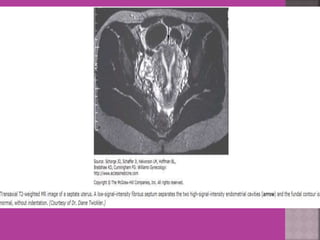

 Congenital uterovaginal anomalies—

bicornuate, septate,subseptate ,

unicornuate, didelphys ,rudimentary horn

and vaginal atrasia etc

 MRI Is more accurate and informative in diagnosis of

congenital malformation of genito-urinary tract.